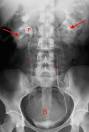

• Kidney, ureter, and bladder (KUB) and upright:

• Indicated primarily if bowel obstruction is suspected

• Air-fluid levels and intestinal distention:

• Bowel obstruction

• Ileus

• Volvulus

• Intussusception

• IVP:

• Indicated in patients with suspected ureteral calculi

• More time-consuming than spiral CT